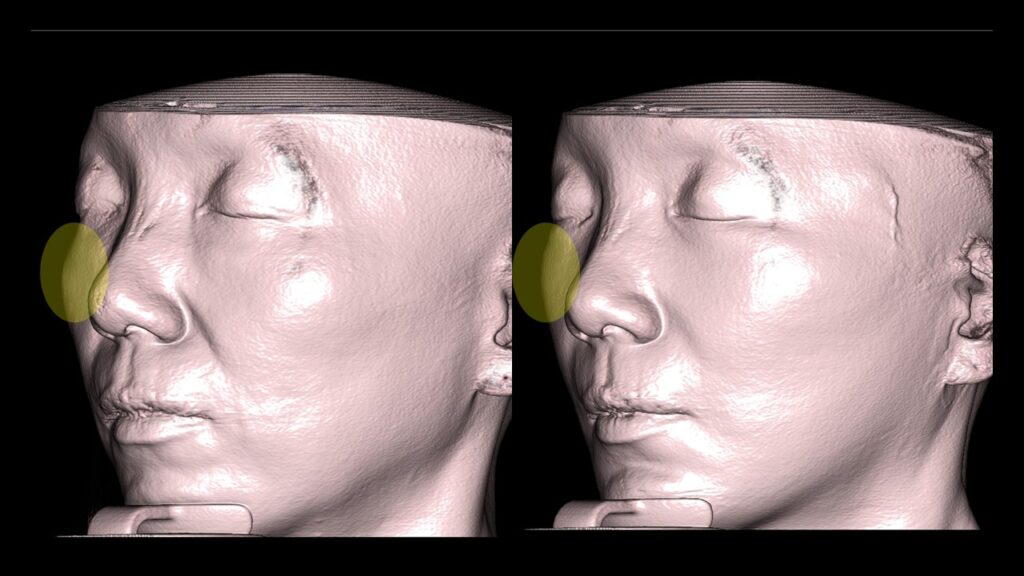

4. Case Studies (3DCT & Medical Photos)

-

Case 1: (Zygoma Reduction + Face Lift) 1-year post-op shows a significant reduction in mid-face width and improvement in nasolabial folds.